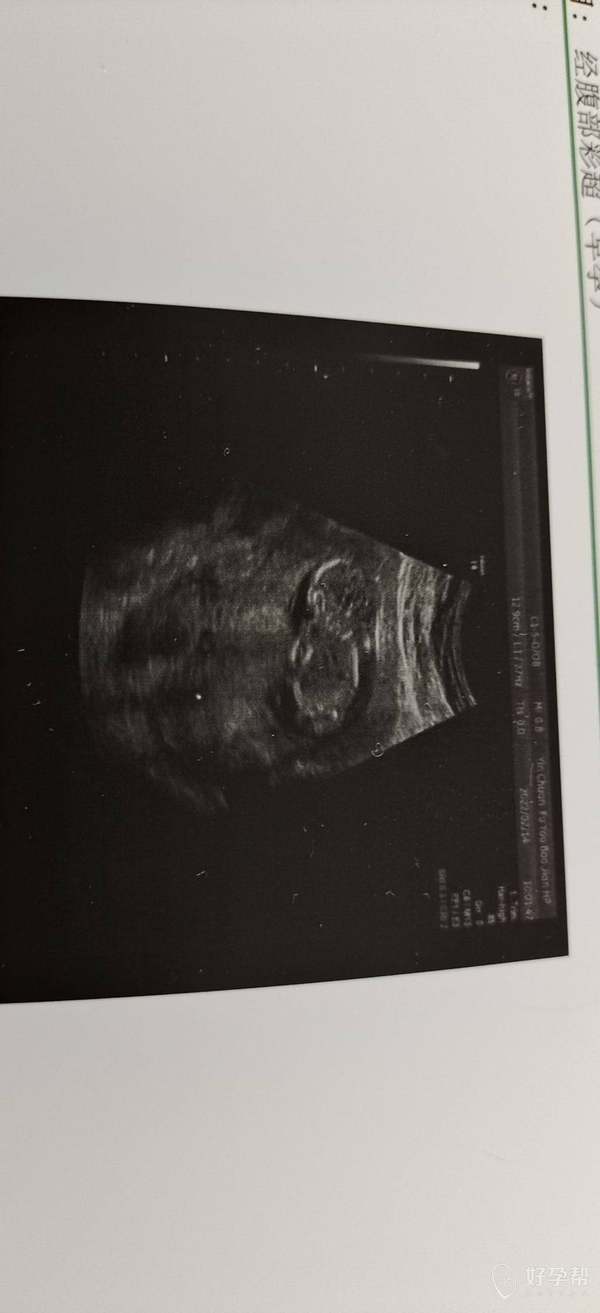

试管移植今天按末次月经算是3个月零5天子宫内

积液量不大,可以暂时不用管它,让它自己吸收的,你现在就按医嘱先用保胎药物吧,后期随访观察,一旦出现腹痛加剧或者出血立即就诊就行了。目前在家里保胎吧,多休养,禁止同房!